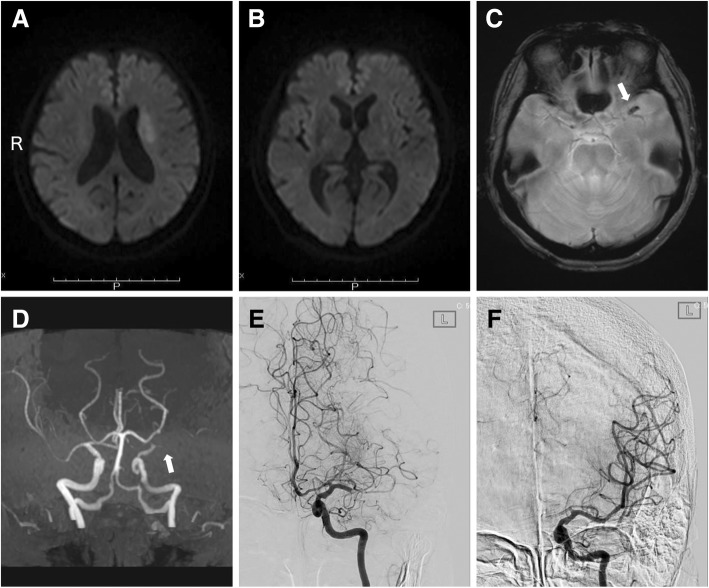

We immediately performed magnetic resonance imaging following the stroke management protocol in our institute. Diffusion-weighted imaging showed hyperintense lesions at the left basal ganglia and corona radiata (Fig. 2a, b). A susceptibility vessel sign was seen in the proximal portion of the left middle cerebral artery (Fig. 2c). Magnetic resonance angiography revealed proximal occlusion of the left middle cerebral artery (Fig. 2d). Alteplase at a dose of 0.6 mg/kg (the dose approved in Japan) was administered 43 min after hospital arrival [2, 3], immediately followed by endovascular thrombectomy as bridging therapy [4]. After thrombectomy with a stent retriever (Solitaire 2, 4 × 20 mm; Medtronic, California, USA), complete recanalization was obtained 95 min after hospital arrival (Fig. 2e, f). Cardiac rhythm monitoring during the endovascular procedure did not show significant findings other than the tachycardic atrial fibrillation.

Fig. 2.

Diffusion-weighted magnetic resonance imaging showing acute infarction at the left corona radiata (a) and left basal ganglia (b). (c) T2*-weighted imaging showing a susceptibility vessel sign (white arrow) in the left middle cerebral artery. (d) Magnetic resonance angiography showing proximal occlusion (white arrow) of the left middle cerebral artery. (e) Anteroposterior view of a selective left internal carotid angiogram showing occlusion of the left middle cerebral artery. (f) Left internal carotid angiogram, anteroposterior view, showing complete recanalization of the left middle cerebral artery